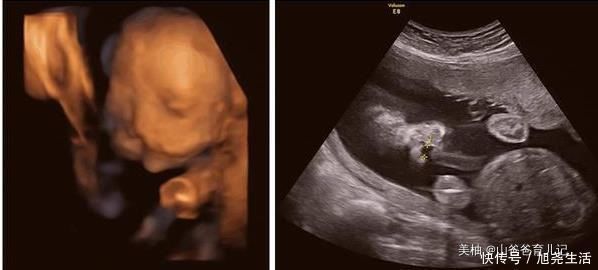

小郭因为是第一次怀孕,和老公来到医院做了B超检查后,竟然是两个孩子,以为那肯定就是双胞胎,高高兴兴的回家了,并且将这个喜讯告诉了家里人,婆婆听说后,更是激动的第二天就从乡下过来照顾小郭。

但是手术并不顺利,小郭进去了很长时间,全家人也等的十分焦急,开始的激动心情变得忐忑不安,结果孩子生出来时候,全家乱成一团,确实是两个孩子,但却是连体婴儿,如果做手术,两个孩子将面临很大的风险,还要面对高昂的手术费。